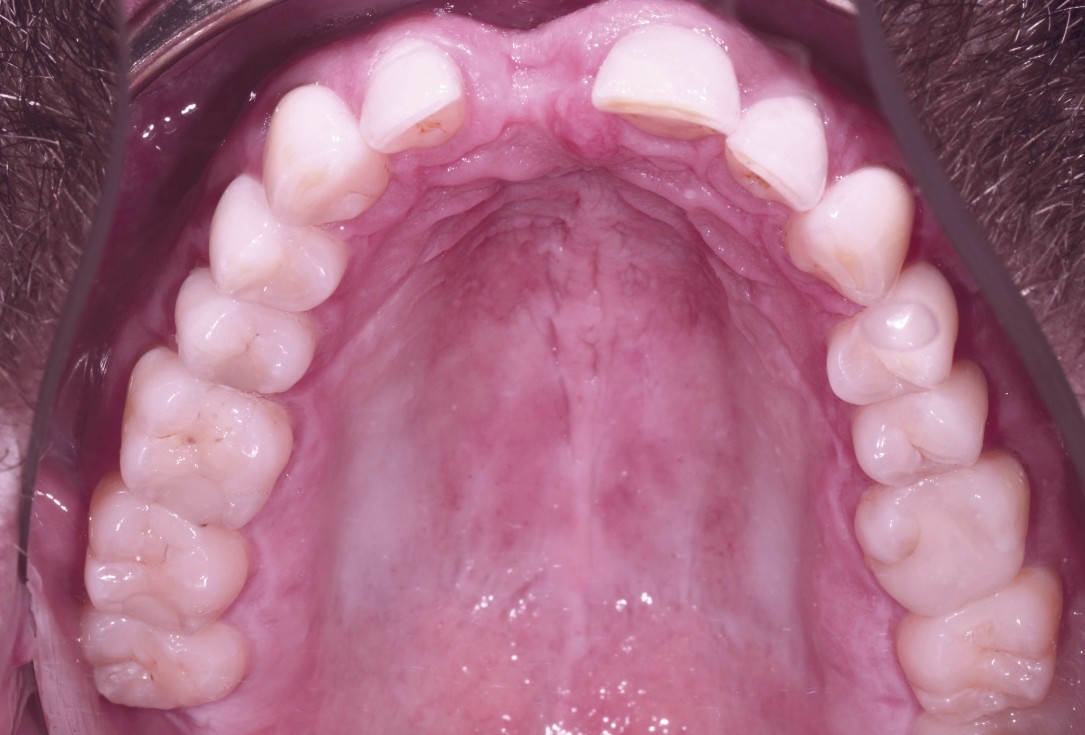

03/18 - Clinical situation after tooth extraction - occlusal view

Block augmentation with maxgraft® and cerabone® – PD Dr. Dr. F. Kloss